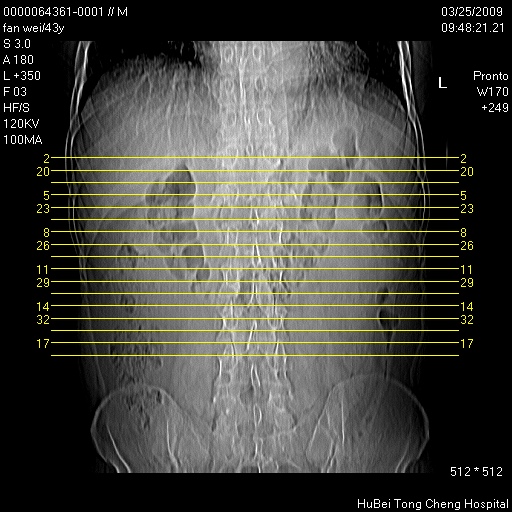

双肾ct轴位平扫+增强扫描(层厚10mm,螺距1.0,重建间隔10mm),图像如下: